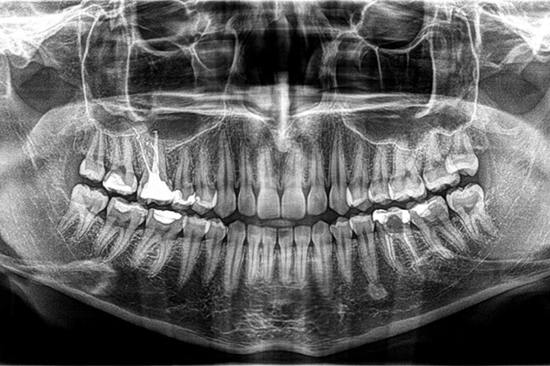

Ortopan CBCT (3D i 2D)

Bez naručivanja i čekanja u 30 sekundi napravit ćemo trodimenzionalnu sliku vaših zubi koju možete dobiti na CD-u ili vam šaljemo na mail.